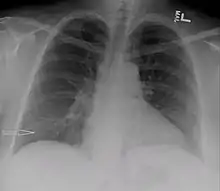

Right sided pleural effusion caused by urinothorax | |